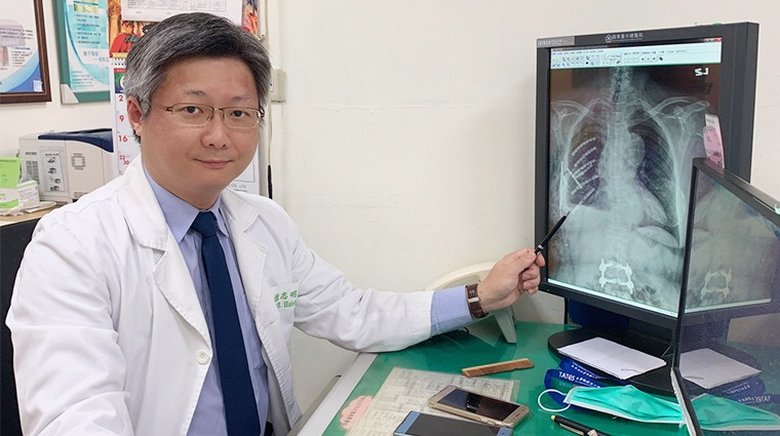

以往早期肺癌或部分中晚期肺癌的手術都需要插呼吸管、胸管、尿管等3管。現在,台大醫院胸腔外科首創的「單孔無管微創胸腔鏡手術」已成為肺癌手術的主流,相關國際期刊超過50篇以上。免插氣管的胸腔鏡手術,不僅減少全身麻醉造成的傷害,還使病患更快恢復。不只麻醉藥用量省、保留更多肺功能,開完刀隔天就能出院。

2020-01-17 18:38:21傳統肺癌手術必須開胸切斷多根肋骨,傷口長達2、30公分,術後還須裝置胸管及尿管,易引起患者疼痛不適,且恢復時間久。台大醫院研發以單孔胸腔鏡手術,搭配免氣管插管麻醉,在病人清醒的情況下精準切除腫瘤,大幅降低術後疼痛。